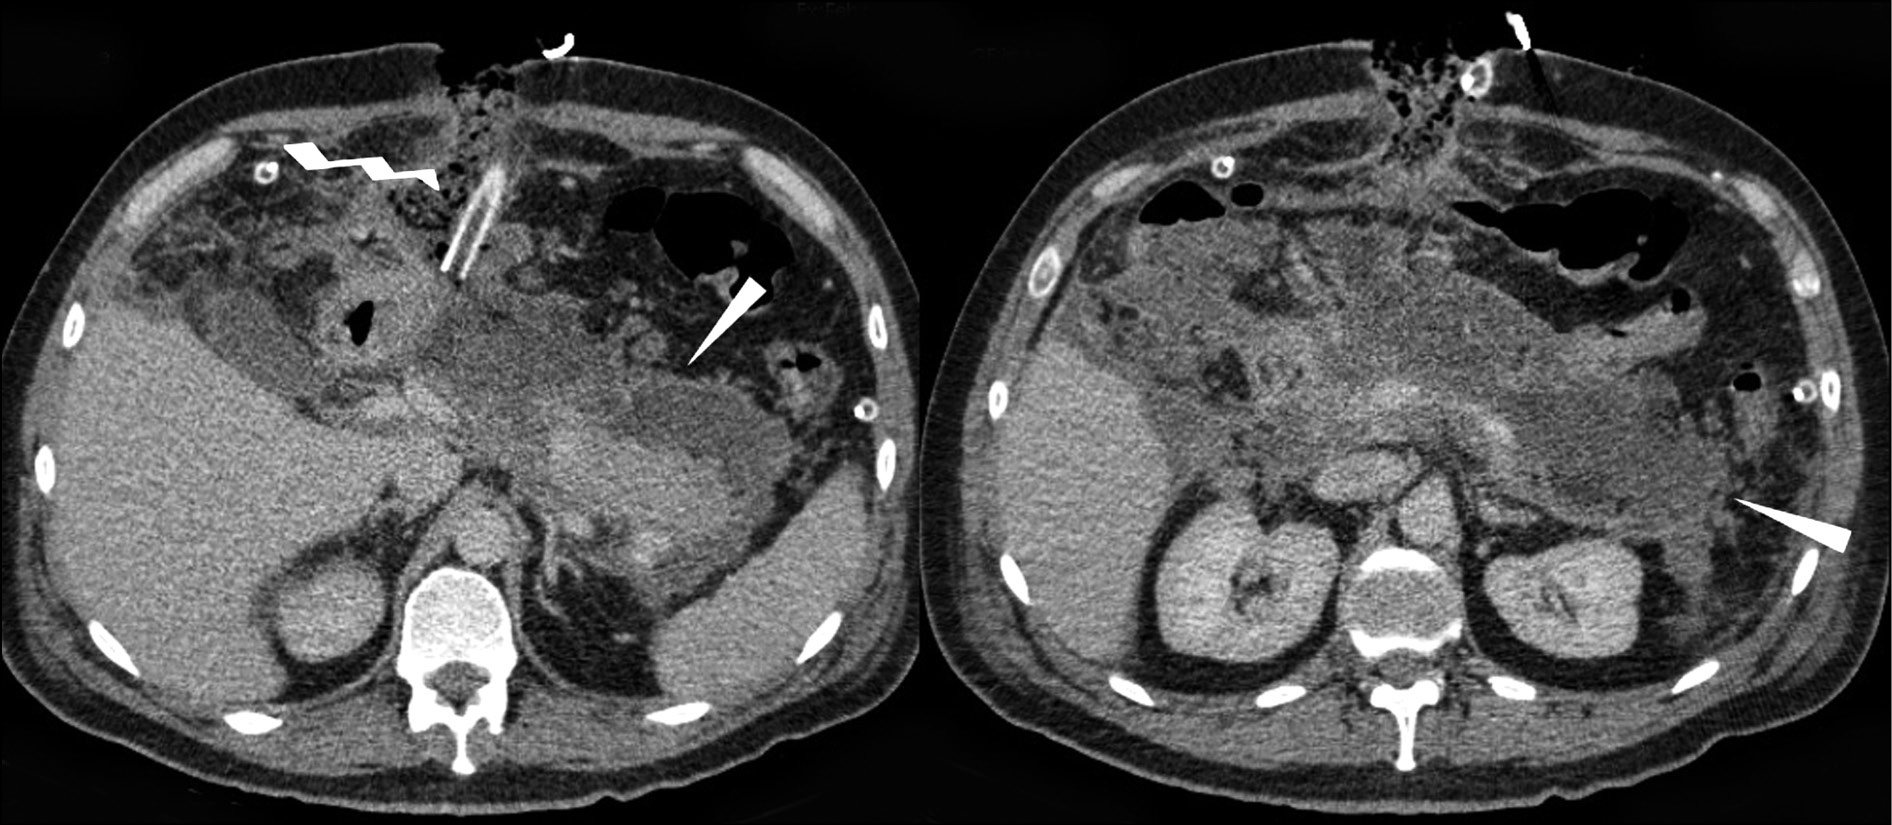

The control TO and AO CT (February 14; February 21, 2018) revealed a decrease in the left-sided hydrothorax and resolution of the area of consolidation in the lower lobe of the left lung, as well as a decrease in effusion in the peripancreatic tissue and infiltrative changes in the fatty tissue of the abdominal cavity (Fig. 4).

Fig. 4. Computed tomography of the abdominal cavity organs with intravenous contrast: enveloped infiltration and fluid accumulation in the peripancreatic adipose tissue, decreased in dynamics (image on the left, arrows), hemostatic sponge in the cavity of the enveloped contents; drainage tube (image on the right, zigzag arrow). Further formation of a thin contrasting capsule along the course of the infiltration zone is noted in the dynamics.